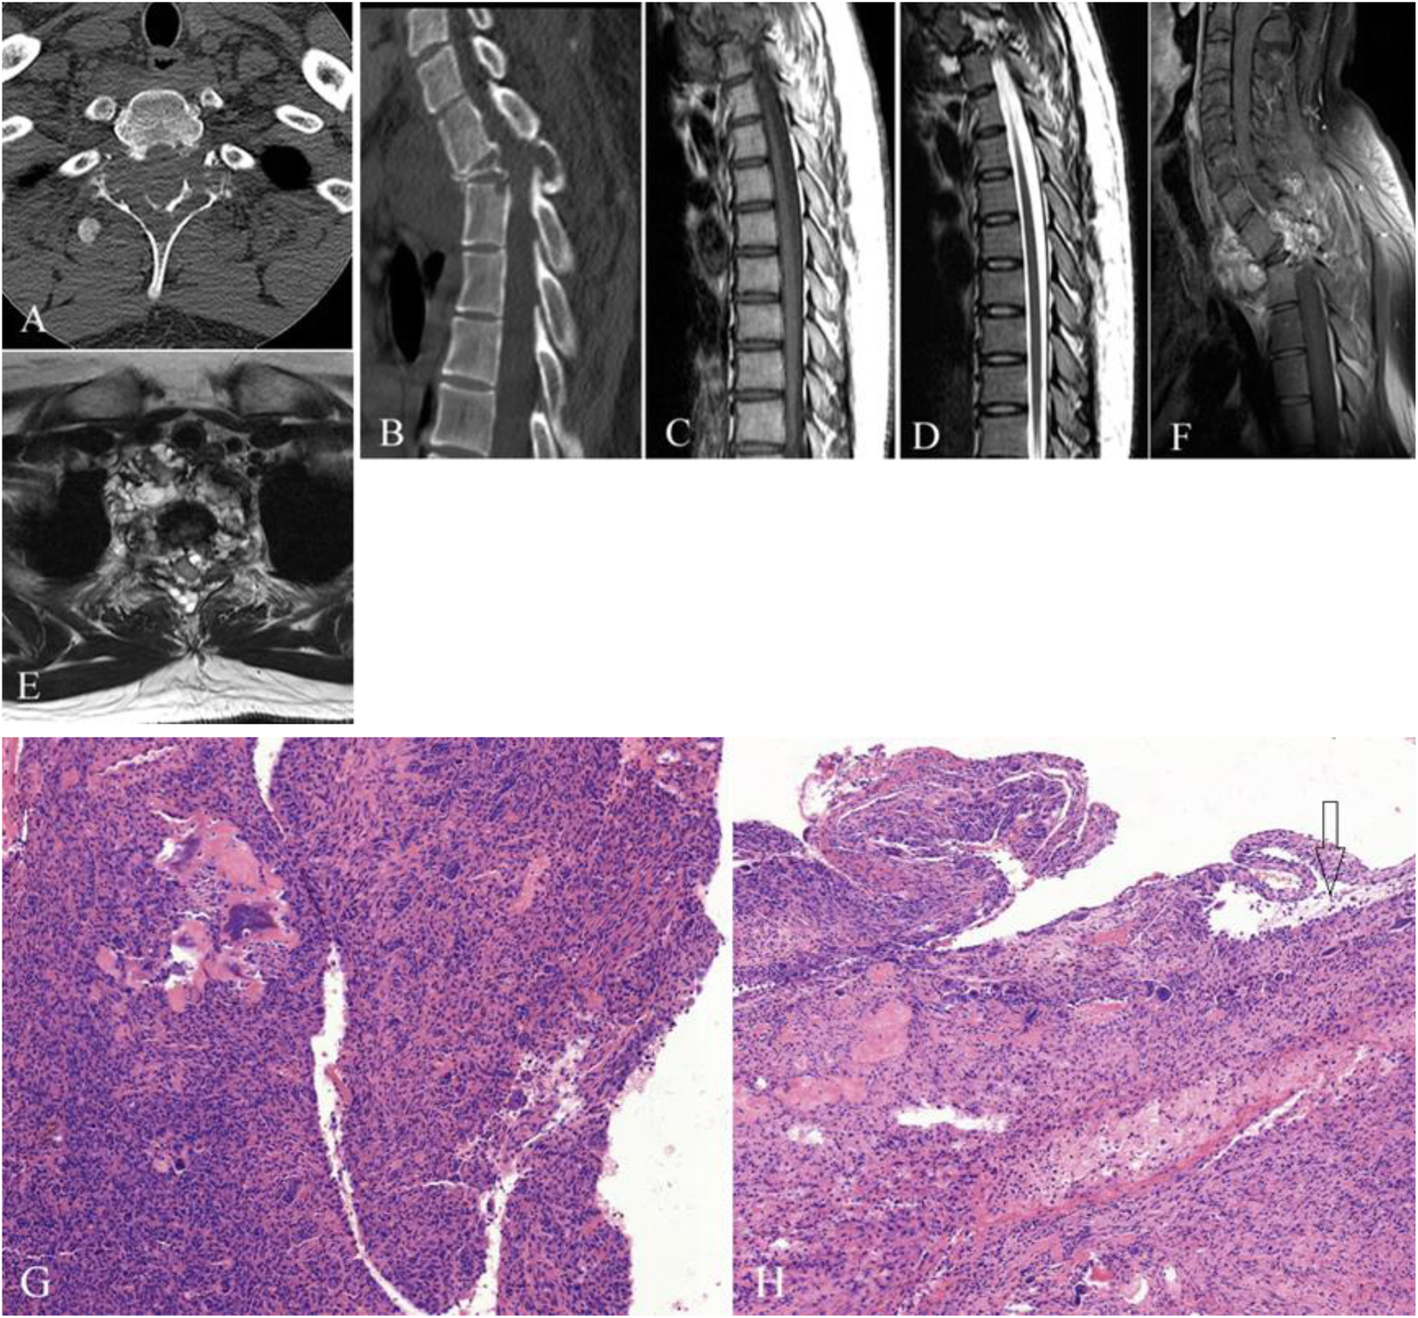

Fig. 3

Giant cell tumor in the T2 vertebra. a Axial CT, b reformatted sagittal plane image, c sagittal plane T1-weighted image, d sagittal plane T2-weighted image, e axial T2-weighted image, and f post-enhanced sagittal and T1-weighted image. a The lesion involved the bilateral lamina and the spinous process with an ill-defined margin. b T2 vertebral body collapse and lesion invasion into the anteroposterior T3 vertebra. c–e MRI showing multiple cystic components and fluid–fluid levels that compressed the dural sac. f The solid component showed significant enhancement on post-enhanced image. Photomicrograph (100× magnification) demonstrating (g) a multinuclear giant cell and (h, arrow) an aneurysmal bone cyst component showing cyst-like changes, intracavitary bleeding, and no endothelial cells in the wall